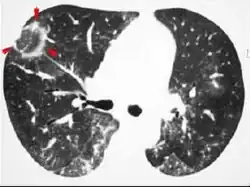

Imaging

The chest x-ray is distinctive with features that appear similar to an extensive pneumonia, with both lungs showing widespread white patches. The white patches may seem to migrate from one area of the lung to another as the disease persists or progresses. Computed tomography (CT) may be used to confirm the diagnosis. Often the findings are typical enough to allow the doctor to make a diagnosis without ordering additional tests.[19] To confirm the diagnosis, a doctor may perform a lung biopsy using a bronchoscope. Many times, a larger specimen is needed and must be removed surgically.

Plain chest radiography shows normal lung volumes, with characteristic patchy unilateral or bilateral consolidation. Small nodular opacities occur in up to 50% of patients and large nodules in 15%. On high resolution computed tomography, airspace consolidation with air bronchograms is present in more than 90% of patients, often with a lower zone predominance. A subpleural or peribronchiolar distribution is noted in up to 50% of patients. Ground glass appearance or hazy opacities associated with the consolidation are detected in most patients.

Unusual presentations of organizing pneumonia

While patchy bilateral disease is typical, there are unusual variants of organizing pneumonia where it may appear as multiple nodules or masses. One rare presentation, focal organizing pneumonia, may be indistinguishable from lung cancer based on imaging alone, requiring biopsy or surgical resection to make the diagnosis.[20]